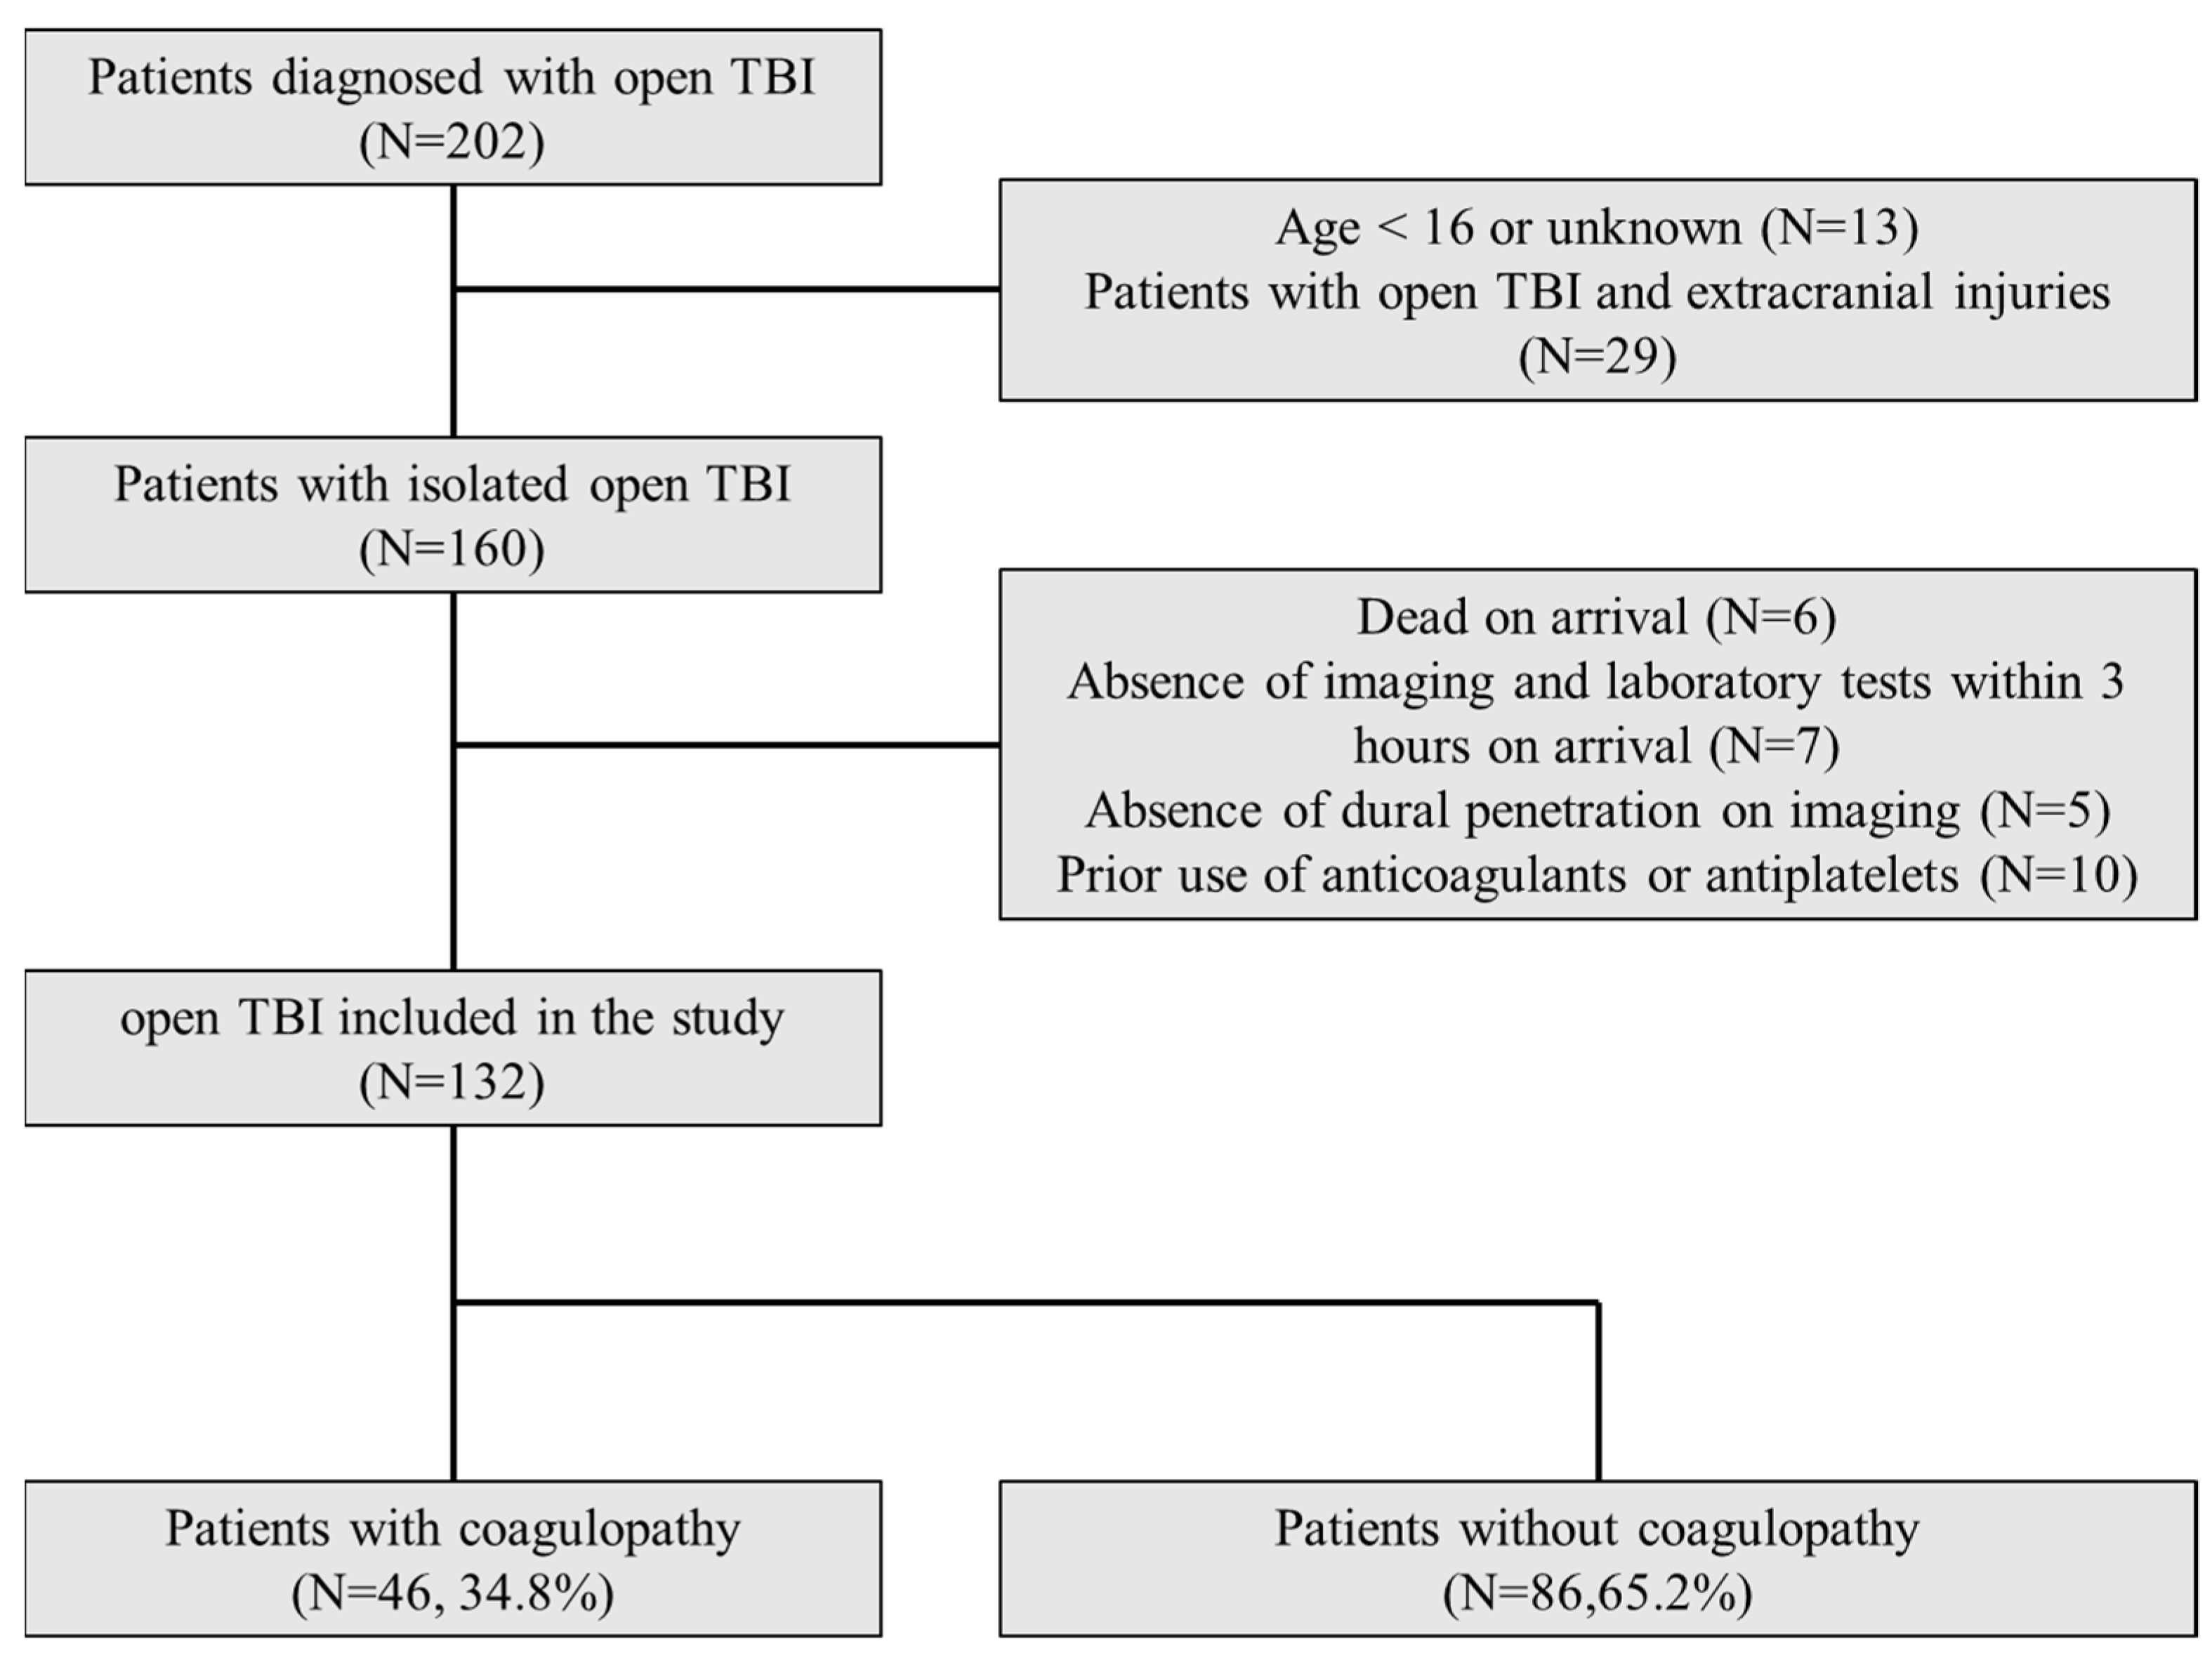

7.1. Subject Recruitment